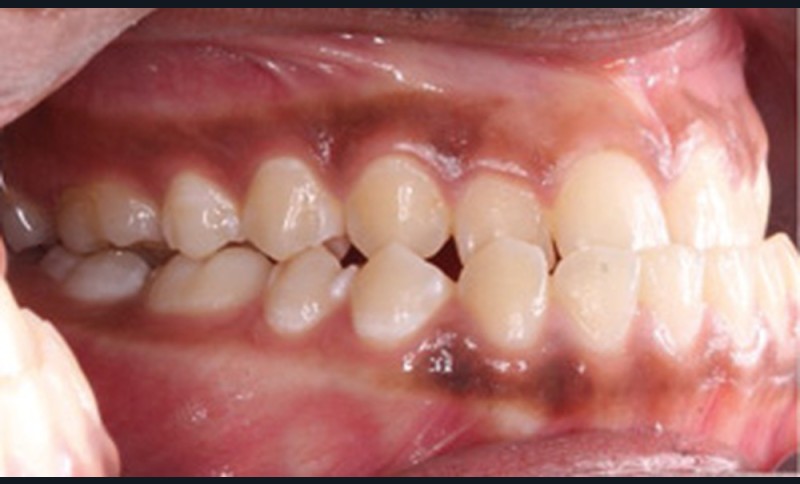

Examen clinique (fig. 1a-h)

À l’examen de face, Anisa présente un visage ovalaire, des hémifaces symétriques, des lignes horizontales parallèles, une augmentation de l’étage inférieur, une occlusion labiale légèrement forcée et des dents mandibulaires exposées au sourire. Les profils général et sous-nasal sont concaves avec un angle naso-labial augmenté et une prochéilie inférieure.

L’examen clinique endo-buccal révèle une denture adulte jeune avec un inversé d’articulé antérieur de 13 à 23, des tatouages gingivaux ethniques et des taches de décalcifications, un parodonte sain mais un brossage insuffisant.

L’arcade maxillaire est en V et la voûte palatine profonde. L’arcade mandibulaire a une forme en U (non-concordance des formes d’arcade) et présente des malpositions des dents cuspidées. La médiane mandibulaire est décalée à gauche de 2 mm ; le recouvrement antérieur est de 2 mm ; les molaires sont en classe III avec un surplomb inversé.